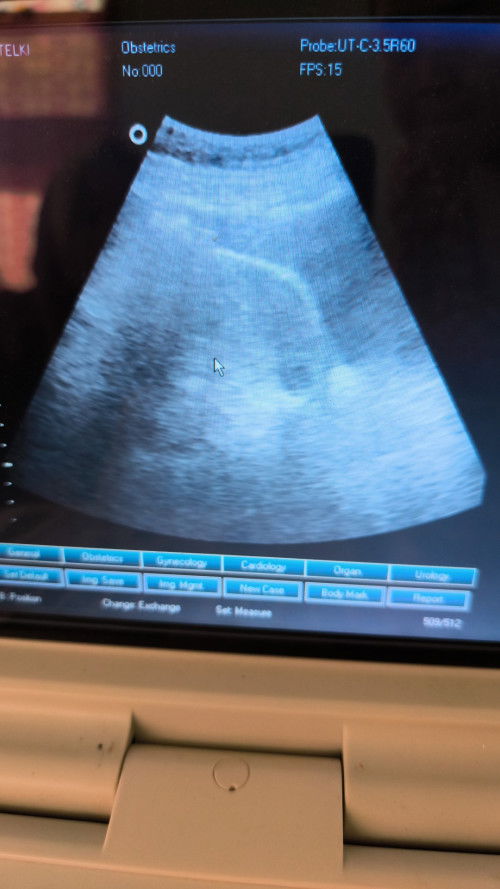

Kiranya ada udah ada kantong ny blm ya

Gimana ada bisa baca USG

waktu usg gak dijelasin sama dokternya ? gak tanya juga kedokternya ?? usg bayar mahal² harusnya dikasih tau hasil usgnya